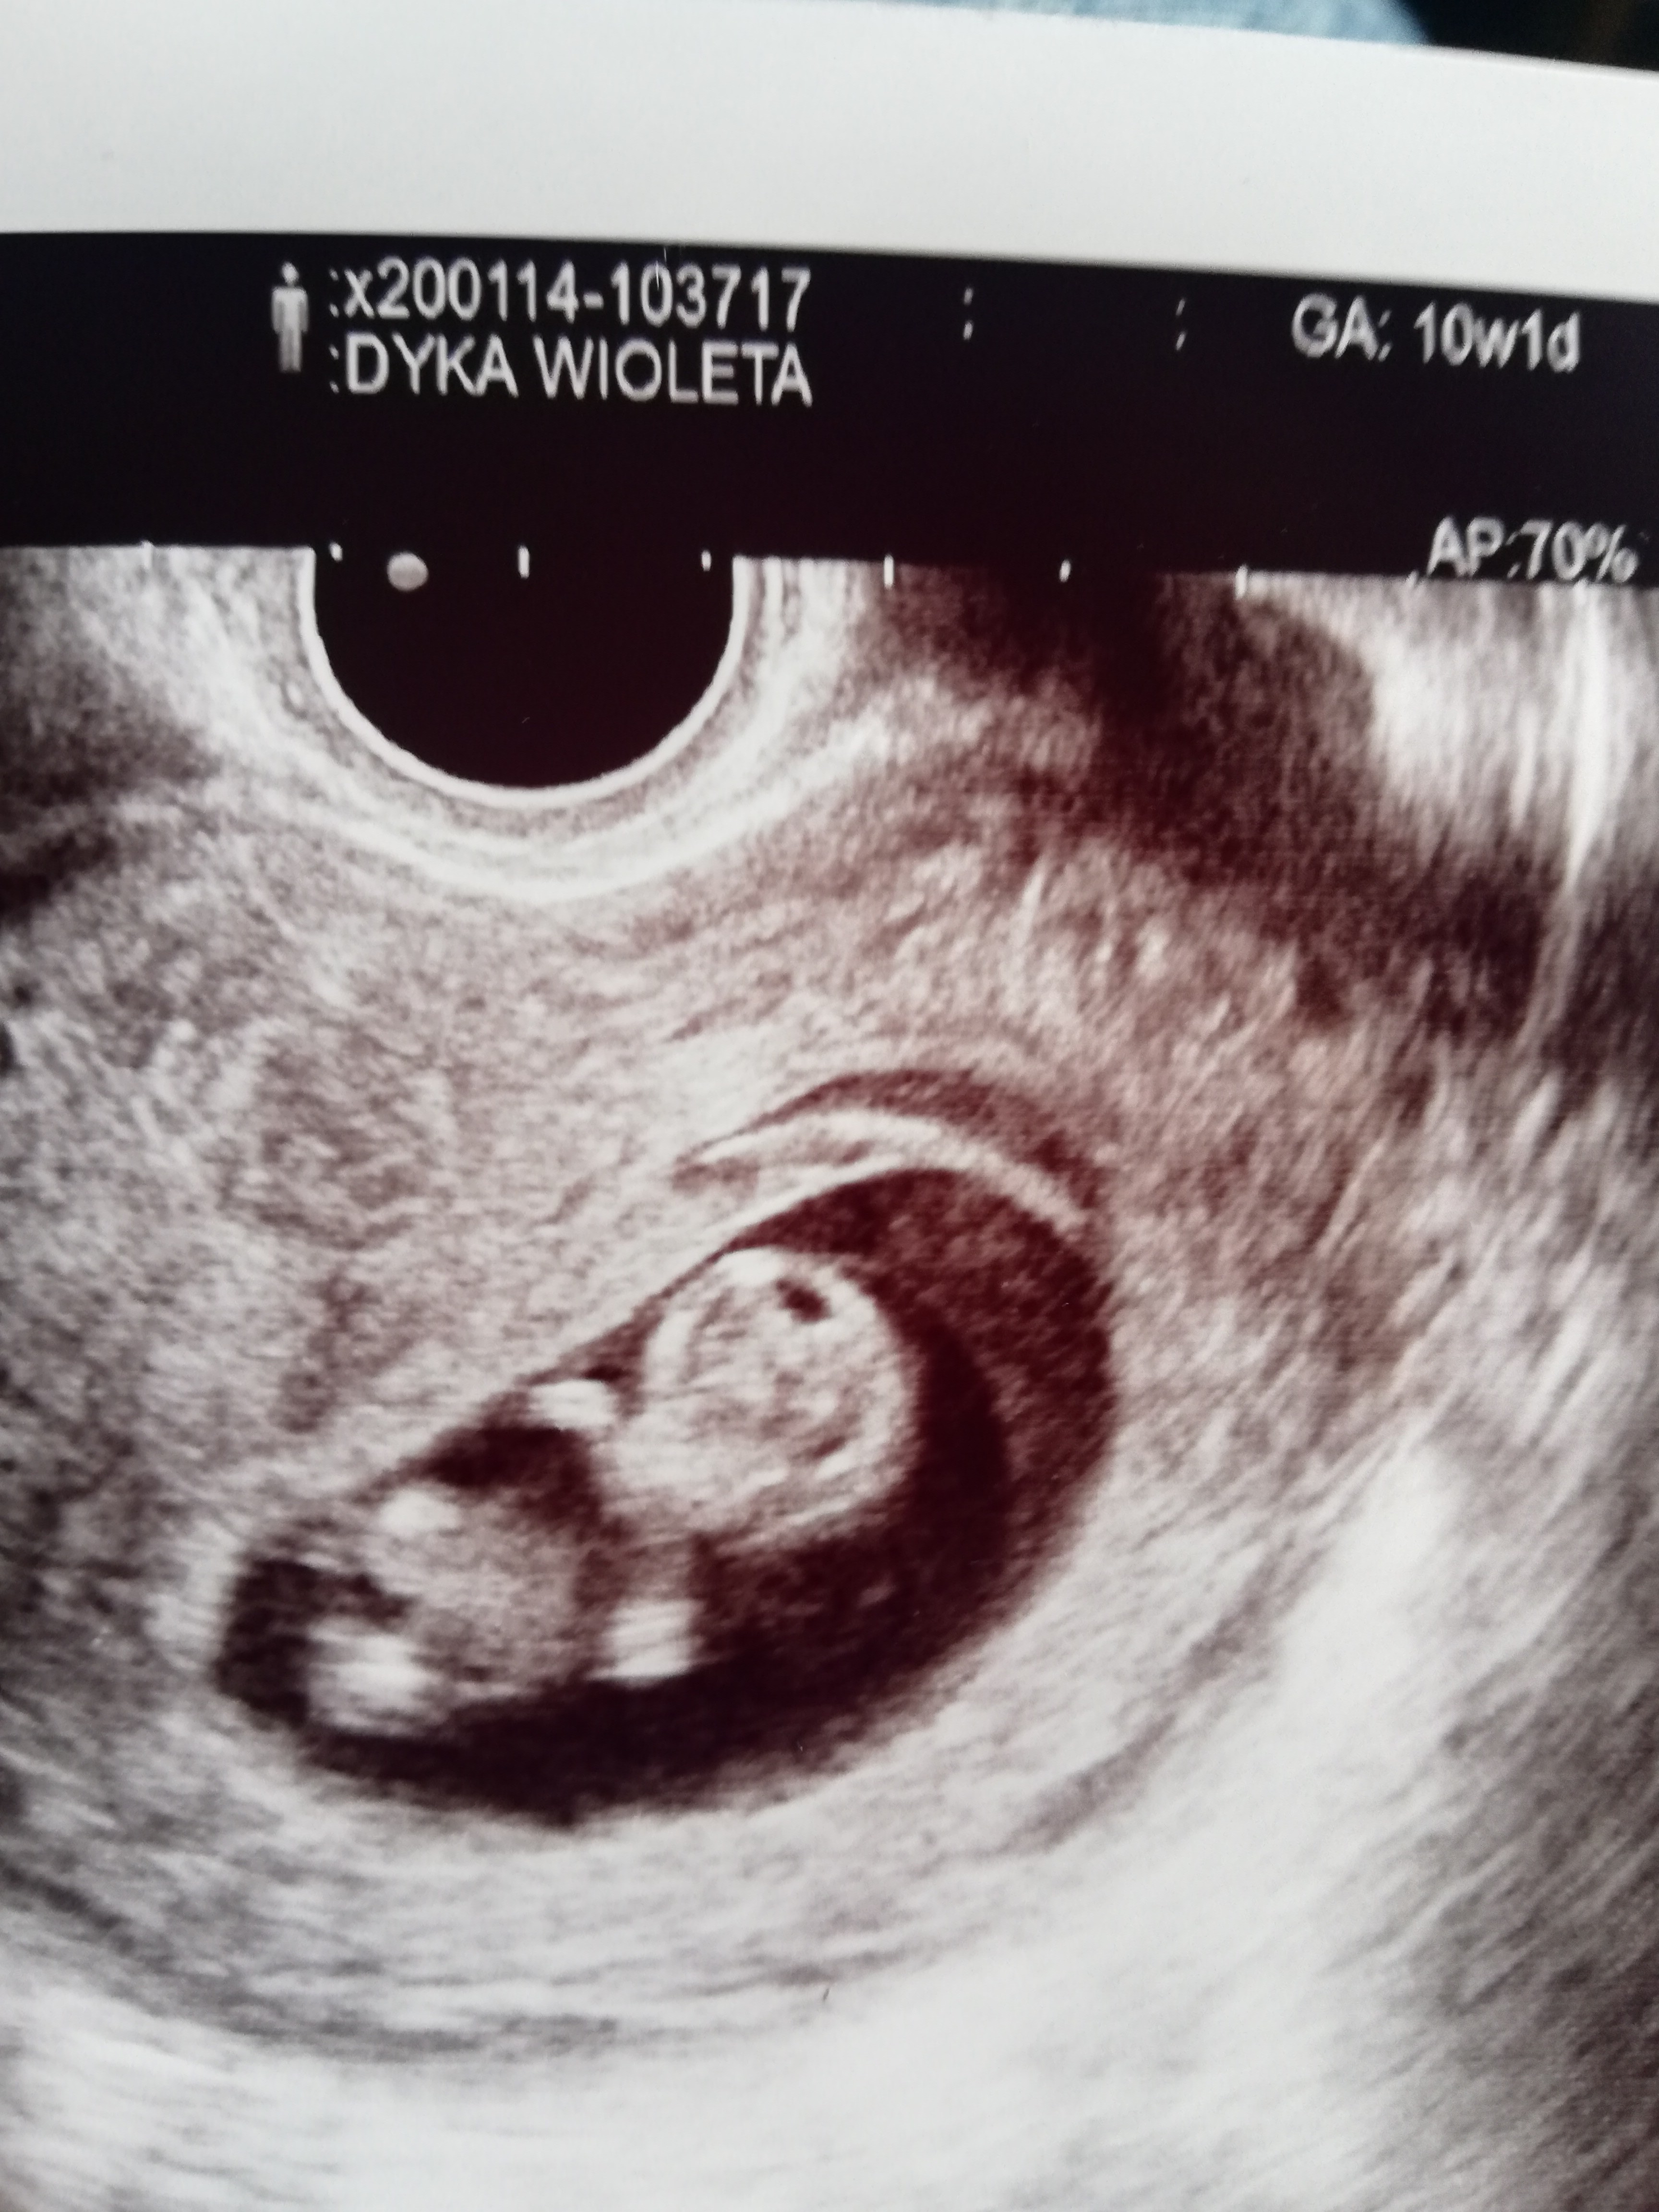

Ja już po wizycie. Serduszko bije i na razie wszystko ok, jedno duże zagrożenie już mija a jeszcze do 15, 16 tygodnia dopóki się nie wytworzy łożysko to jeszcze zagrożenie jest, ale na razie jest wszystko dobrze. Serduszko bije 170, mam dzisiaj 10+1 a dzidzia duża na 10 +5, pomimo że dziś wszystko ok to z tyłu głowy mam,, dopóki się nie wytworzy łożysko jest ryzyko,, Dudusia idź na l4 będziesz miała spokojniejsza głowę. Dołączam zdjęcie dzidzi

• IMG_20200114_132909.jpg

IMG_20200114_132909.jpg

1,8 MB · Wyświetleń: 111